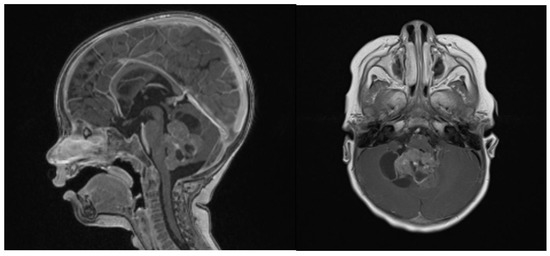

At the last follow-up at 23 months old, the patient did not show any sign of recurrence, with stable enhancing tissue on the floor of the IVth ventricle. Clinical examination was normal, as was global development (as stated by a consultant infantile neuropsychiatrist) (Figure 7). No adverse or unanticipated events were assessed. In this particular situation, local proton therapy (according to the ACNS0333 trial) was recommended [24].

Figure 7.

14 months post-operative gadolinium T1 sagittal and axial sequences, showing no signs of recurrence.